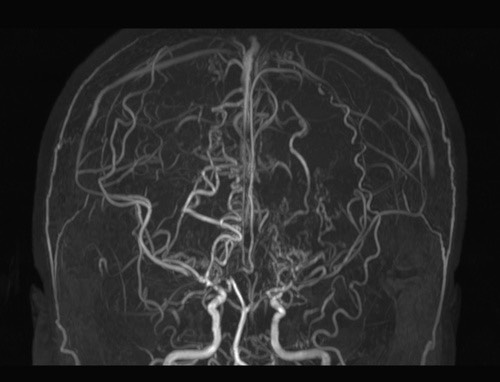

모야모야병은 뇌혈관, 특히 뇌로 혈액을 공급하는 내경동맥과 그 주변 주요 혈관이 점점 좁아지고 막히는 희귀 난치성 질환으로, 혈류가 줄어든 뇌는 부족한 혈액을 보충하기 위해 가느다란 미세측부혈관들을 새로 만들어냅니다. 이 작은 혈관들이 연기처럼 보인다고 하여 일본어로 ‘모야모야(안개·연기)’라는 이름이 붙었습니다. 소아부터 성인까지 폭넓게 나타나며, 특히 5~10세 어린이와 30대 전후의 여성에서 비교적 많이 발견되는 경향이 있습니다. 증상은 일시적 마비, 언어장애, 두통, 실신, 경련 등 매우 다양해 뇌졸중과 유사하거나 초기에는 가벼운 신경학적 증상으로만 나타나 진단이 늦어지기도 했습니다. 질환이 진행하면 허혈성 뇌졸중(뇌경색)이나 출혈성 뇌졸중 위험이 증가하여 반드시 전문적인 관리가 필요합니다. 아직 완전히 예방할 수 있는 방법은 없지만 조기 진단과 적절한 치료를 통해 뇌 기능을 보호하고 삶의 질을 유지할 수 있습니다.

모야모야병은 뇌기저부의 주요 혈관이 서서히 협착되고 막히면서 뇌혈류가 감소하는 만성 진행성 뇌혈관 질환입니다. 협착이 진행된 부위를 대신해 뇌는 생존을 위해 얇고 약한 혈관망을 만들어 혈류를 보충하려 하고, 이 새로운 혈관들이 촬영 영상에서 연기처럼 퍼져 보인다고 하여 ‘모야모야’라는 이름이 붙었습니다. 기전적으로는 내경동맥 말단부와 중대뇌동맥·전대뇌동맥의 기시부에 병변이 가장 잘 생기며, 시간이 지남에 따라 양쪽에 대칭적으로 나타나는 특징을 보였습니다. 이 질환은 단순한 혈관 협착이 아니라 진행성 변화이기 때문에 치료하지 않으면 혈류 부족이 심해지고 뇌 손상이 누적될 수 있습니다. 또한 뇌기능이 체력·호흡·체온 변화 등에 민감하게 반응하기 때문에 과호흡, 울음, 격렬한 운동, 감염 등으로 증상이 악화될 수 있습니다. 즉, 모야모야병은 시간이 지나면서 뇌혈류를 감소시키고 뇌졸중 위험을 높이는 질환이며, 평생 관리가 필요한 만성적 특성을 갖고 있습니다.

따라서 가족력이 있거나 의심되는 증상이 있다면 뇌 MRA·MRI 등의 정기검진이 도움이 되며, 조기 진단 시 치료 효과도 훨씬 높아집니다.